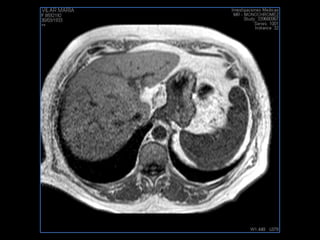

PROTOCOLO hígado graso AXIAL in phase y out phase AX T1 y AX fat sat +SAG T2  CON   GADOLINIO :  COR T1+AX T1(DIN) SAT: NO  FASE: RL THK: 4MM  COIL:  GAP: (FACTOR 1.4)  FOV: 40 CM NEX:2 SINCRONIZACION RESPIRATORIA EN 3 O 4 CICLOS ALE

PROTOCOLO hemocromatosis AXIAL supresión grasa /AX multieco en higado COR T2 AX T1 +SAG T2  CON   GADOLINIO :  COR T1+AX T1 SAT: NO  FASE: RL THK: 4MM  COIL:  GAP: (FACTOR 1.4) 1MM FOV: 40 CM NEX:2 SINCRONIZACION RESPIRATORIA EN 3 O 4 CICLOS ALE

resonancia de abdomen